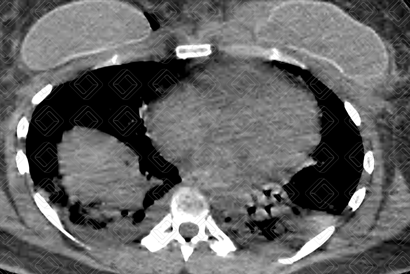

Texto alternativo para a imagem Figura 1. Créditos: Dra. Elazir Mota - Rio de Janeiro/RJ

Descrição das figuras 1, 2 e 3: Tomografia computadorizada de tórax. Consolidações periféricas nos lobos inferiores dos pulmões (setas vermelhas).

• Tomografia computadorizada do tórax: E xame de escolha diante da suspeita clínica. Os achados tomográficos são áreas em vidro fosco e/ou consolidações predominando na periferia do pulmão. Derrame pleural é raro. Esses aspectos de imagem surgem somente após 24-48 horas do quadro (figura 1).